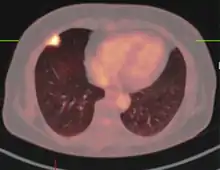

Imaging

The appearance of a tuberculoma on imaging can vary according to the composition and age of the mass. They may appear as either non-caseating or solidly caseating lesions.[20] Initially, tuberculomas appear hypodense on computed tomography (CT) scans with significant surrounding edema.[23][3] The "target sign" is pathognomonic for tuberculoma on CT, with a nodular ring-enhancing mass and central calcification.[24][20] The characteristic ring-enhanced appearance is due to lack of blood supply in the central necrotic core that is visualized with injected contrast.[22] Sometimes a hypodense central area is seen instead of calcification.[25] When considering other potential intracranial masses in a differential diagnosis, such as cysticercosis, pyogenic abscess, and neoplastic lesions, tuberculoma can be identified by its larger size (>2 cm), edema, and irregular border.

Magnetic resonance imaging (MRI) is another useful imaging modality for diagnosing and characterizing of tuberculomas, especially solid caseous necrosis in which 3 zones of varying intensity are seen.[22]